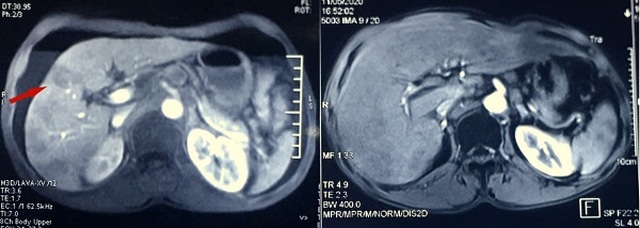

Tại Bệnh viện Ung Bướu Hà Nội, các kết quả cận lâm sàng cho thấy dày thành thực quản 1/3 dưới tạo khối kích thước 5x2,5cm, thâm nhiễm mỡ xung quanh, có nhiều hạch quanh tổn thương, kích thước hạch lớn nhất 2 cm. Đáng nói, ung thư đã di căn gan với ổ lớn nhất đường kính 3cm.

Tại giai đoạn này, các biện pháp điều trị tại chỗ, tại vùng không còn khả thi. Bệnh nhân được chỉ định điều trị hóa chất toàn thân.

Sau chu kỳ đầu tiên, bệnh nhân đáp ứng thuốc và đã có thể nuốt thức ăn. Kết thúc 4 lần truyền, bệnh nhân ăn tốt, tăng cân. Đáng mừng hơn là kết quả xét nghiệm không còn thấy tổn thương di căn gan.